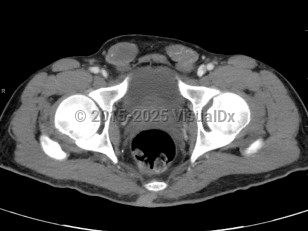

Imaging Studies image of Cryptorchidism - imageId=7904911. Click to open in gallery.  caption: '<span>Axial CT image demonstrates  bilateral extrascrotal testes, located in the inguinal canal. Findings  consistent with cryptorchidism.</span>'

Axial CT image demonstrates bilateral extrascrotal testes, located in the inguinal canal. Findings consistent with cryptorchidism.